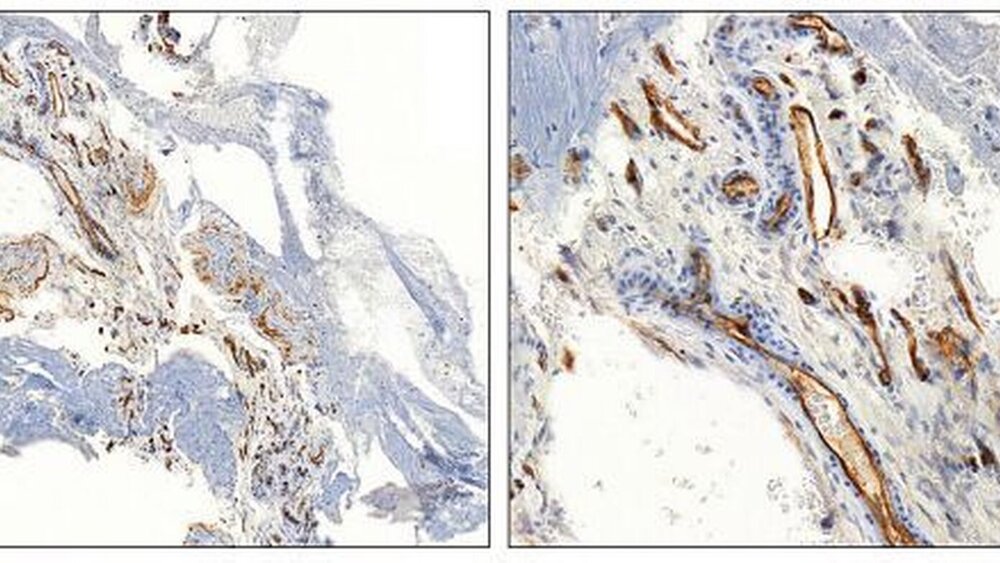

Die histologische Aufarbeitung des Präparats zeigte Fett- und Bindegewebe mit dem Nachweis von großlumigen, wandstarken Gefäßen, ausgekleidet durch regelhaftes zartes Endothel (Abbildung 5). Im Interstitium waren auch Siderophagen erkennbar. In der ergänzenden immunchistochemischen Färbung mit dem Endothelmarker CD34 konnten zahlreiche Gefäßgeflechte nachgewiesen werden (Abbildung 6). Somit ergab sich abschließend in der histopathologischen Begutachtung die Diagnose eines intraossären kavernösen Hämangioms mit regressiven Veränderungen.

Histologisch besteht ein intraossäres Hämangiom typischerweise aus erweiterten, dickwandigen Blutgefäßen die mit roten Blutkörperchen angefüllt sind. Die Blutgefäße zeigen eine stark positive immunhistochemische Reaktion mit den Endothelmarkern CD31 und CD34. Hämangiome lassen sich in kavernöse, kapilläre und gemischte Formen untergliedern. Die überwiegende Zahl der intraossären Hämangiome sind der kavernösen Form zuzuordnen, für die erweiterte, großlumige Gefäße charakteristisch sind. Seltener ist die kapilläre Form, bestehend aus englumigen Kapillaren sowie die gemischte Form, die beide Komponenten aufweist. [Williams et al., 2002; Oliveira et al., 2008; Schwenzer, Ehrenfeld, 2011].